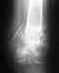

здравствуйте! у меня есть пару вопросов, я сломал ключицу 1й раз со смещением , меня не стали ложить в больницу , сделали колечки ( повязку ) и отправили домой после чего я обследовался у районного травматолога. Ходил навсякие процедуры,контрольные снимки, сменили повязку на болле удобную,и после закрытия справки через 5ть недели сломал заново тоесть в общей сложности я отходил 6 недель как положено с повязкой и на 11й недели сломал заново. На этот раз меня положили в больницу, таже ситуация была с небольшим смещением, на счет операции ничего не говорили,после выписки, я опять же наблюдался у травматолога на процедуры не ходил так как сессия не позволяла. сейчас я уже закрыл 2ю спраку даты переломов такие 9 сентября и 24 ноября,дискомфорта никакого не ощущаю рука полностью функционирует,а вот как поведет себя при тяжелых нагрузках незнаю. Соответствено такие вопросы :1) за какое сростается ключица?2)через какое время и какие нагрузки можно на нее оказывать?(качалка) 3)можно ли было делать операцию? за счет государства или же за мой? 4)какие лекарства посоветуете пить чтоб были крепкие кости?или для профилактики вот снимки

• Кликните для загрузки файла 28112007(001)1.JPG